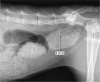

Figure 6

Ventrodorsal pelvic radiograph after colonography (1 day after admission at our referral centre). Rectal stricture of 2 mm can be seen due to abduction of the right femur. Sacral index of 0.07. Narrowing of the pelvic canal of 93%. R = right; L = left